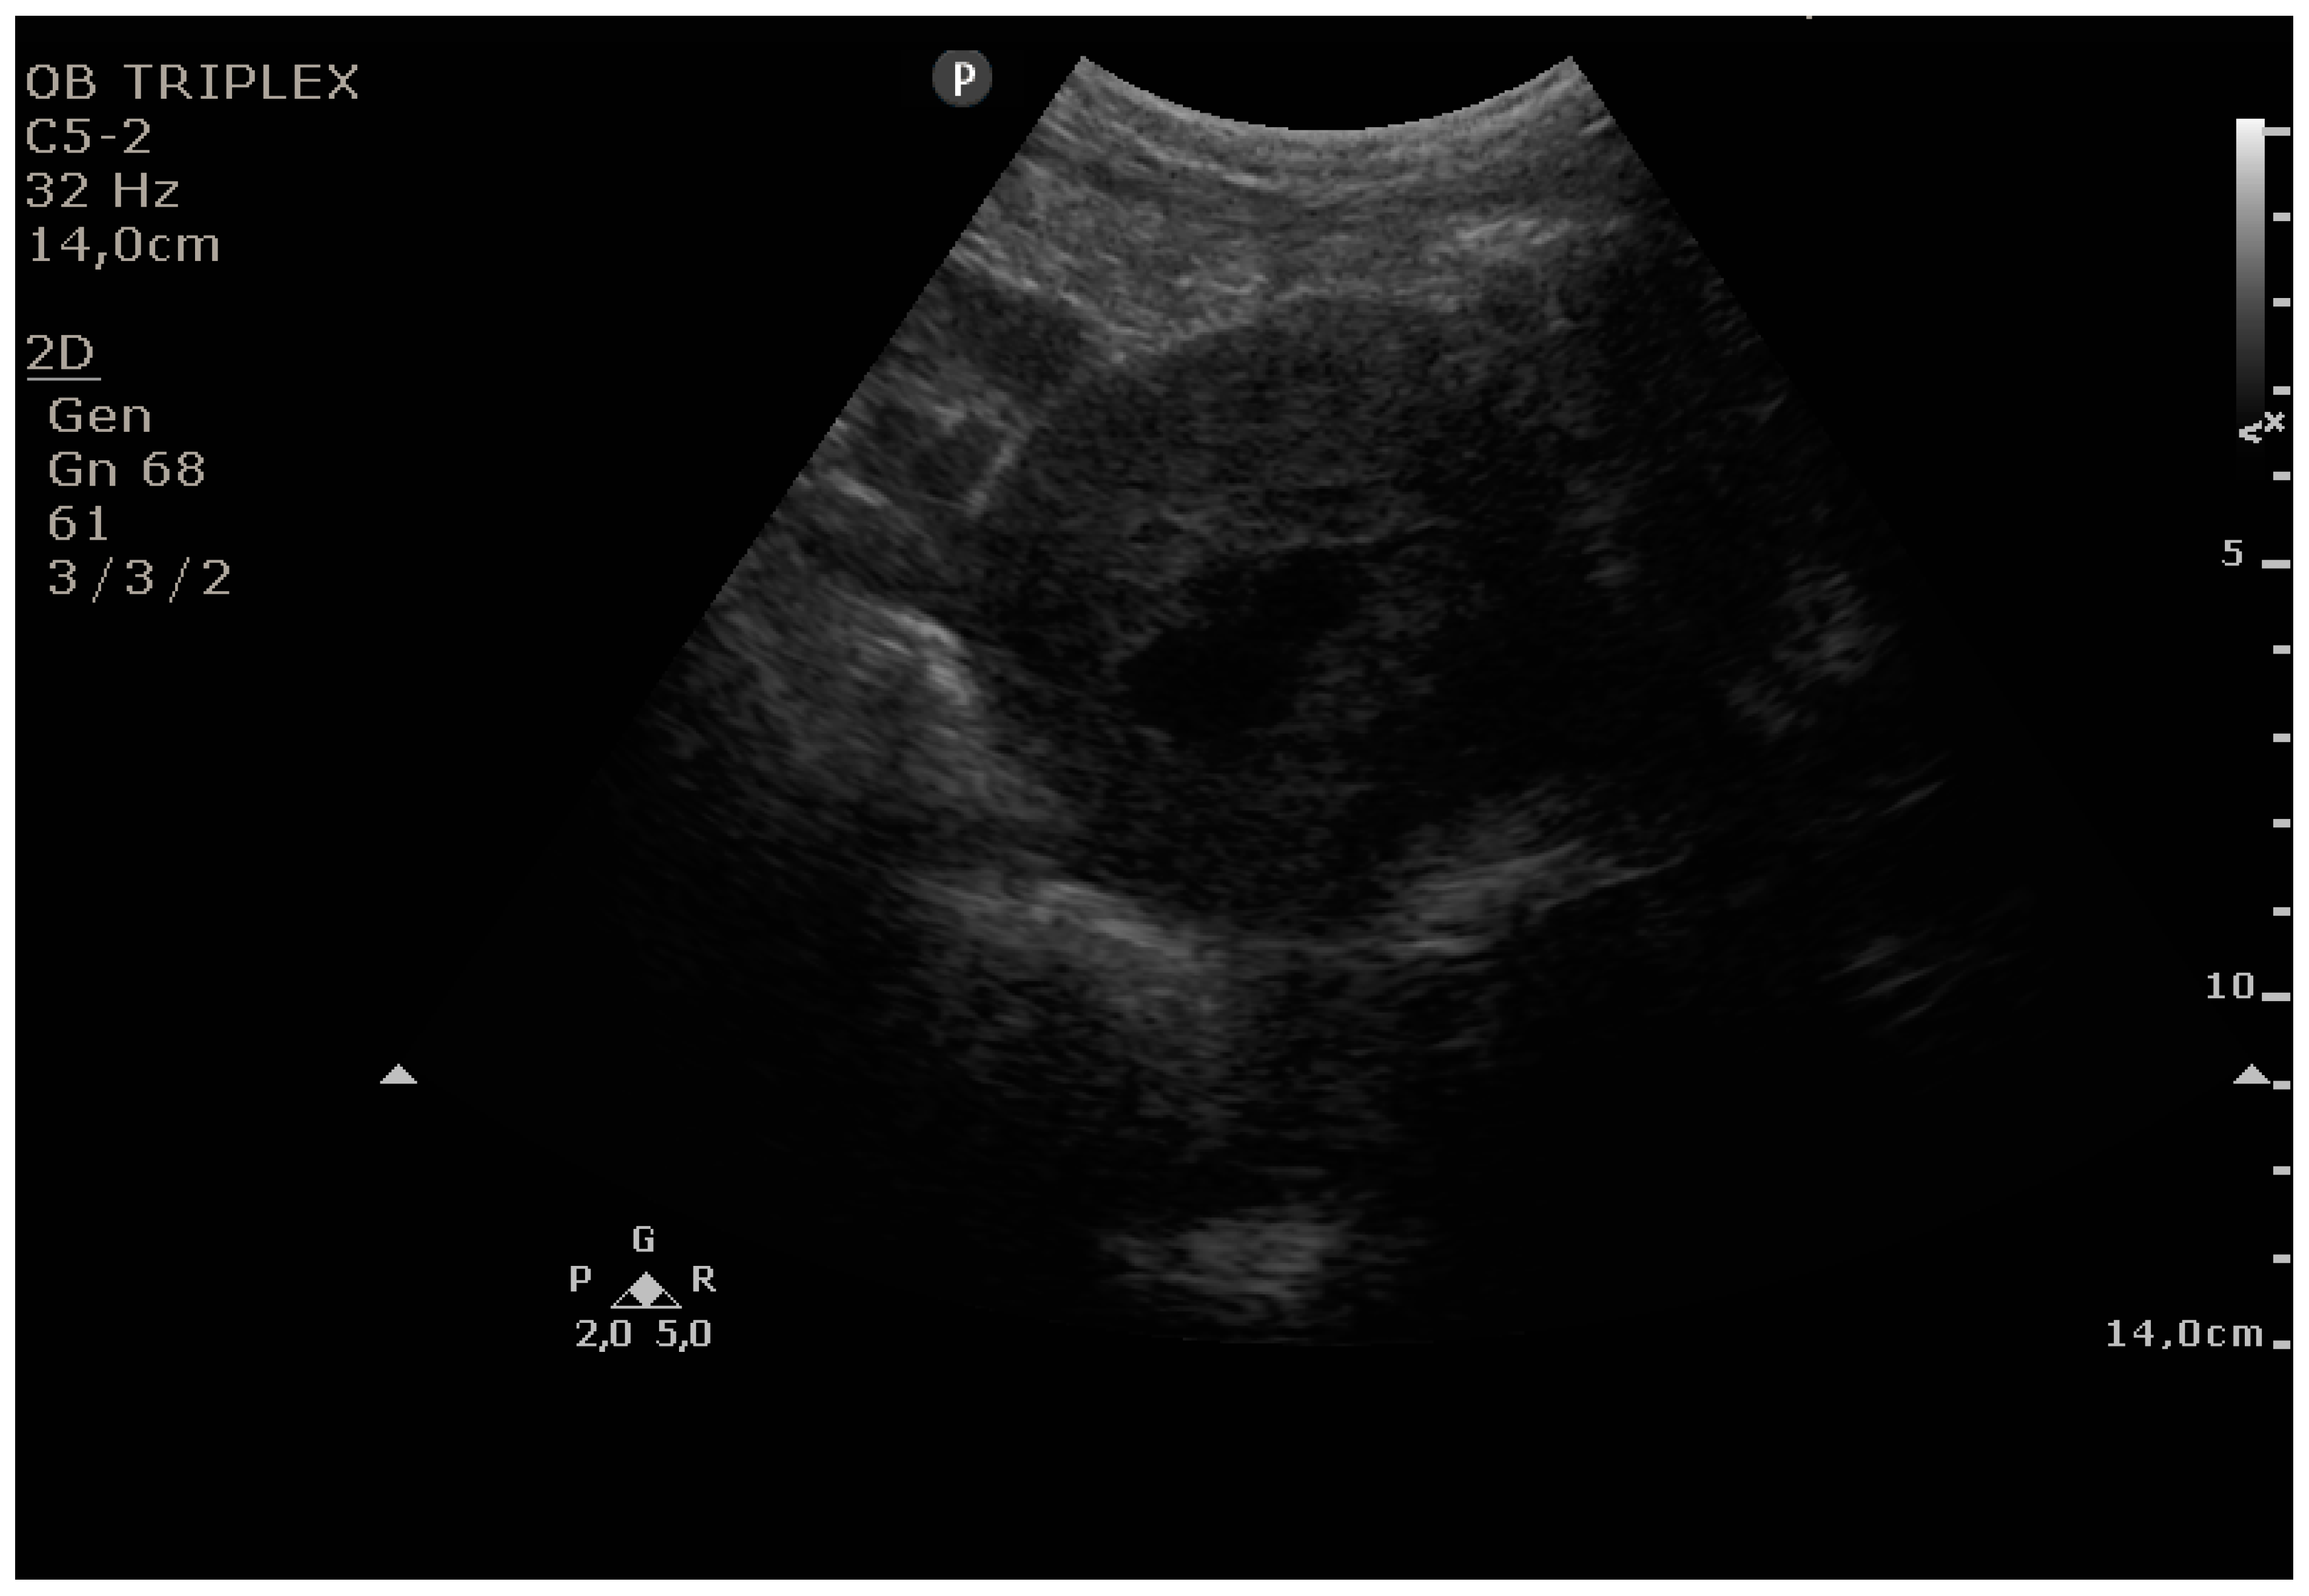

The PUUS method evaluates the proportion of the endometrial length occupied by blood or debris, as follows (Figure 1, Figure 2, Figure 3, Figure 4 and Figure 5):

Figure 1.

Grade 0: no blood or debris in the uterine cavity.

Figure 2.

Grade 1: less than one-quarter of the endometrial length occupied by blood or debris.

Figure 3.

Grade 2: less than one-half of the endometrial length occupied by blood or debris.

Figure 4.

Grade 3: less than three-quarters of the endometrial length occupied by blood or debris.

Figure 5.

Grade 4: over three-quarters of the endometrial length occupied by blood or debris.